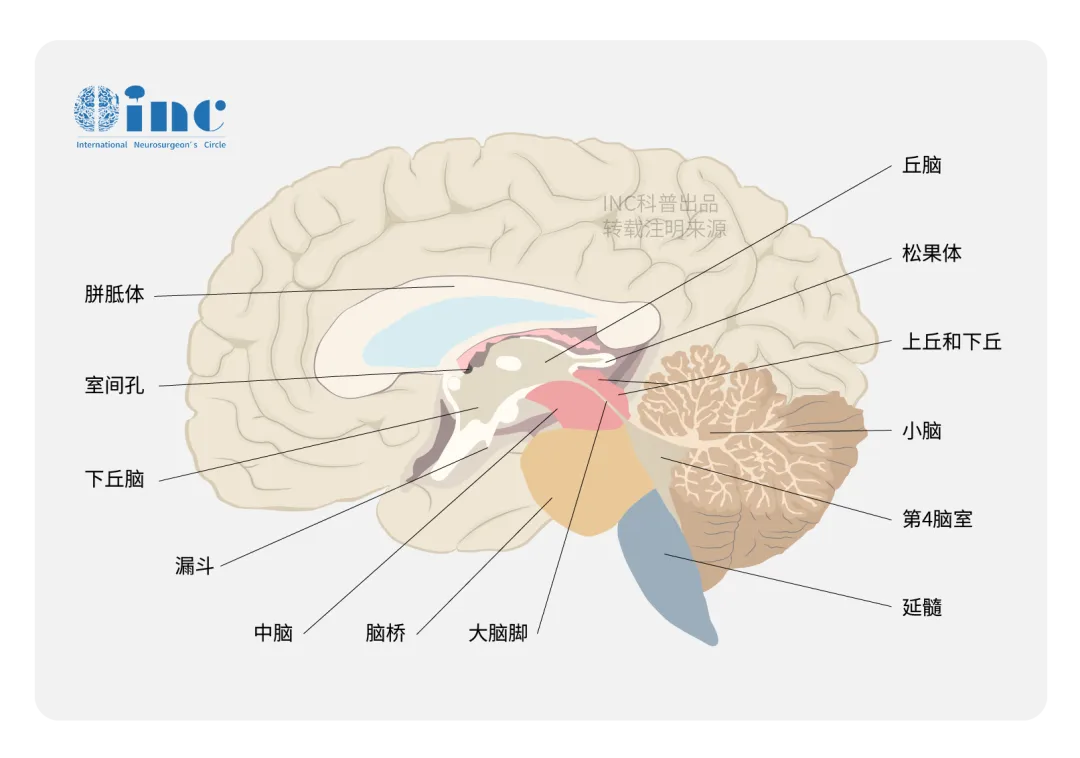

这个案例出自INC福洛里希教授发表的学术论文《Interhemispheric Transcallosal Interforniceal Approach for Retroforaminal Colloid Cysts of the Third Ventricle: Technical Note & Case Series》。...